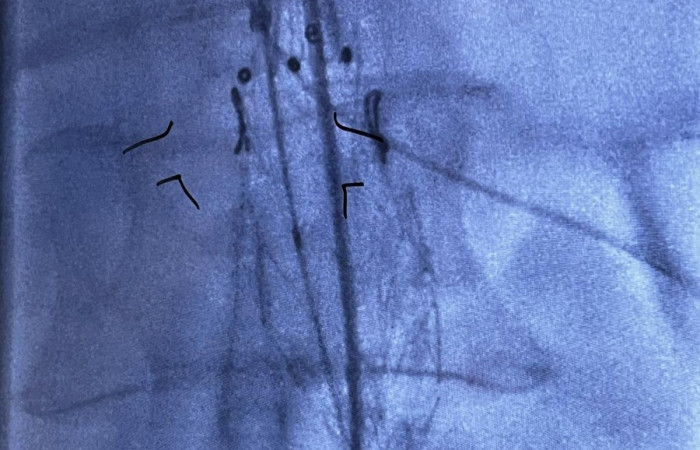

Z dumą dołączamy kolejną innowacyjną metodę do naszego portfolio wysokospecjalistycznych operacji. Wszystko dzięki współpracy pomiędzy Oddziałem Klinicznych Chirurgii Naczyniowej a Pracownią Obrazowania Medycznego 3D przy Zakładzie Diagnostyki Obrazowej NSSU, które umożliwiło postawienie kolejnego kroku naprzód w małoinwazyjnej technice operacyjnej implantacji fenestrowanego stentgraftu do tętniaka aorty brzusznej.

Widoczna na zdjęciach matryca aorty wydrukowana została z żywicy fotopolimerowej, która przeszła proces sterylizacji plazmowej. Użycie technologii 3D umożliwiło indywidualne dostosowanie implantowanego stentgraftu do anatomicznych warunków odejścia naczyń trzewnych od aorty, co z kolei pozwoliło na zakwalifikowanie chorego do małoinwazyjnej procedury zaopatrzenia tętniaka aorty piersiowo brzusznej metodą wewnątrznaczyniową w trybie przyspieszonym.